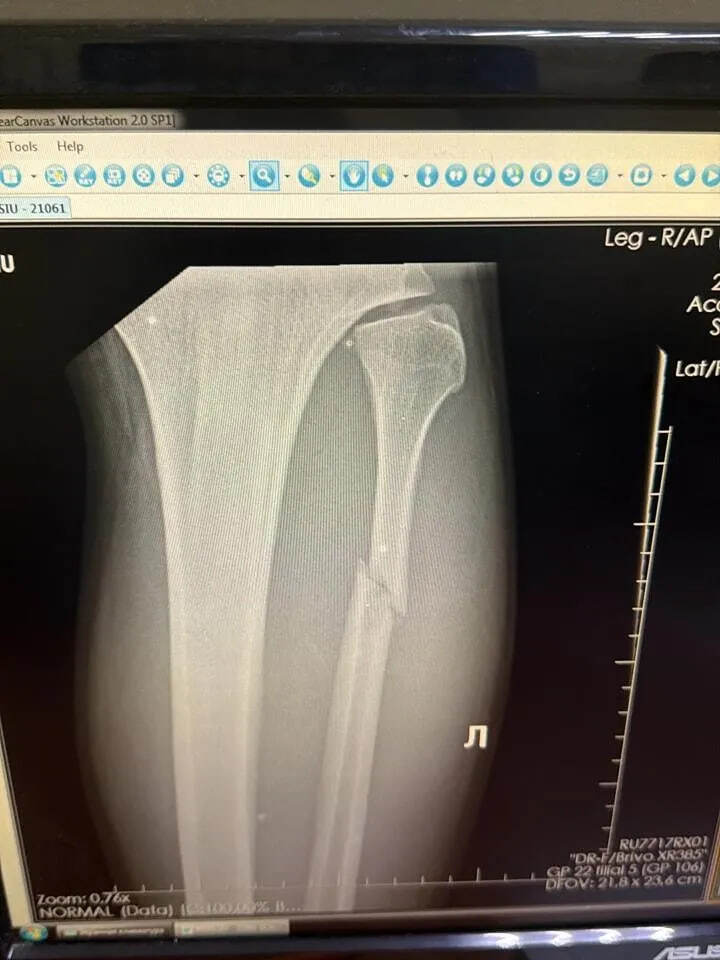

"Хотите стать бойцом UFC?", – написал Уокер под фотографией с рентгена.

Теперь боец передвигается на костылях, ему предстоит тяжелое восстановление, которое займет порядка 5-6 недель. Хотя сам Вальтер признался, что это того стоит.